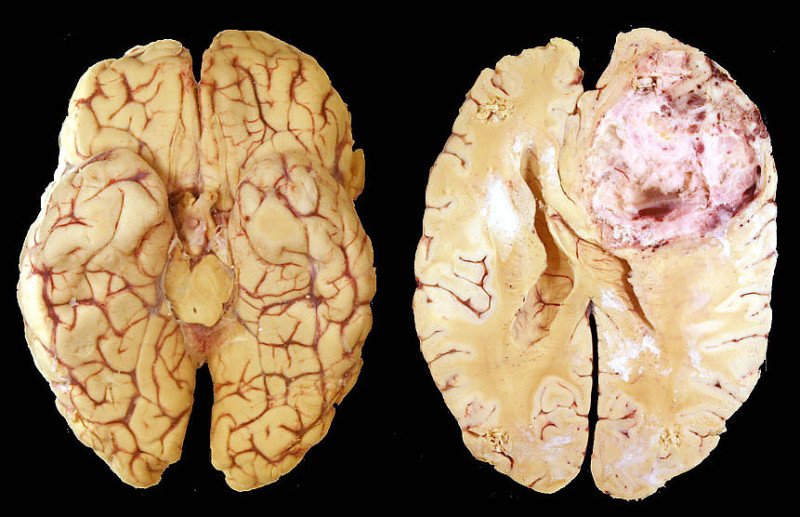

Глиобластома головного мозга: полное руководство по диагностике и лечению

Столкнулись с диагнозом глиобластома? Эта статья поможет разобраться в заболевании, современных методах диагностики, вариантах хирургического и медикаментозного лечения, а также прогнозах и способах поддержки пациентов и их семей.